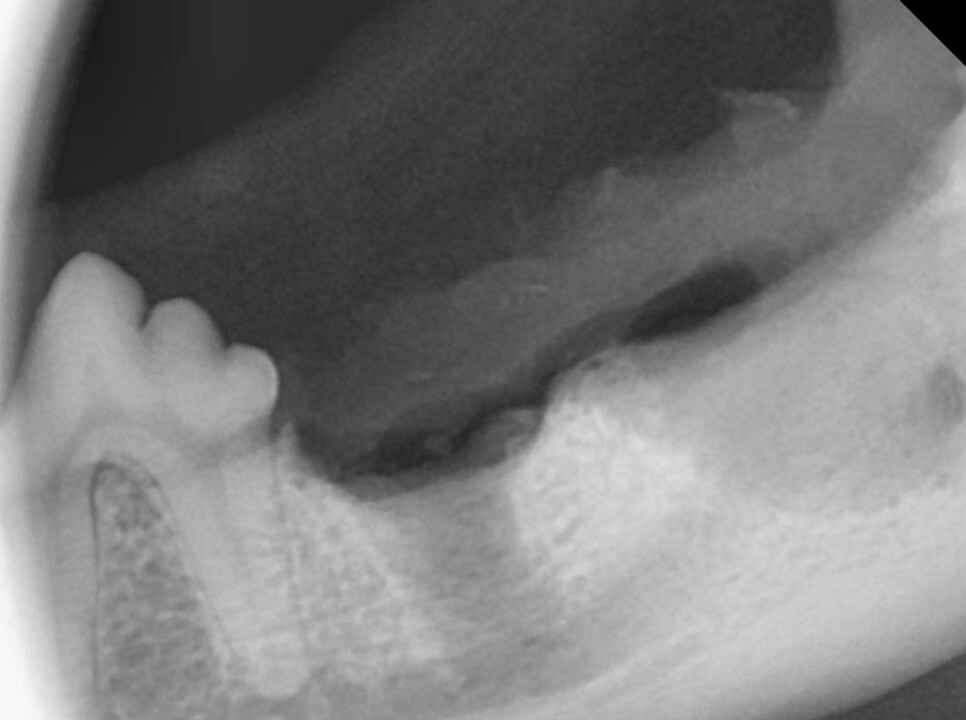

원인을 제거하였기 때문에 종양처럼 병변의 재발을 걱정할 필요는 없습니다. 하지만, 안타깝게도 반대쪽 치아에도 병변이 진행되고 있었습니다.

그나마 다행인 것이 반대쪽의 경우 진행 초기라

합성 뼈를 이식하는 것으로 치료를 할 수 있었습니다.